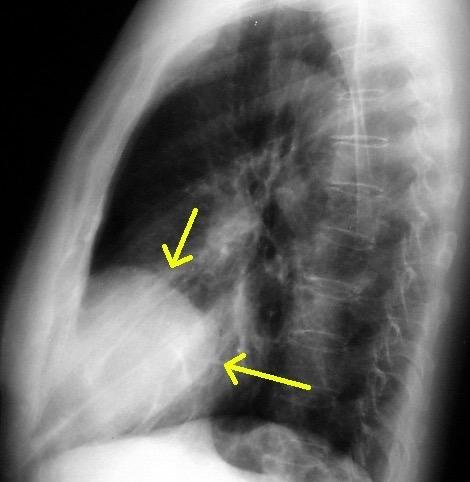

“Draped aorta”.

Indica rotura aórtica reciente. Se manifiesta por una pared aórtica posterior o el contacto con el borde lateral vertebral borrados por la hemorragia.

A. Yudin, Metaphorical

Rotura aneurisma de Aorta descendente.